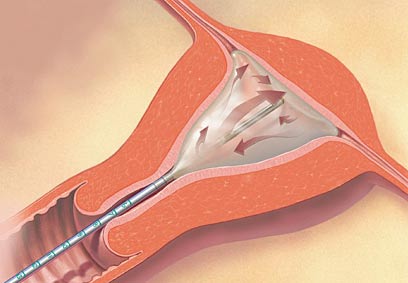

Thermachoise. רירית הרחם המדממת נהרסת.

הטיפול להפחתת הדימום המוגבר, שהגיע ארצה לפני שלוש שנים, מיועד לנשים בעלות חלל רחם תקין, שסיימו את תכנון הילודה. הטיפול נעשה באמצעות מתקן הקרוי Thermachoise המיוצר ע"י חברת "גאיינקייר". המתקן מיועד לטיפול בשכבת הרירית של הרחם בלבד באמצעות חום ומבוצע בהרדמה מקומית, או מלאה.

במהלך הטיפול מוחדר לרחם דרך הנרתיק בלון רך וגמיש המחובר לצינורית הדקה. הבלון מנופח בנוזל סטרילי, כך שיתאים עצמו לגודל וצורת הרחם. הנוזל בבלון מחומם למשך 8 דקות הטיפול באופן מבוקר על ידי מחשב, שבמהלכו נהרסת שכבת רירית הרחם האחראית לדימום המוגבר.